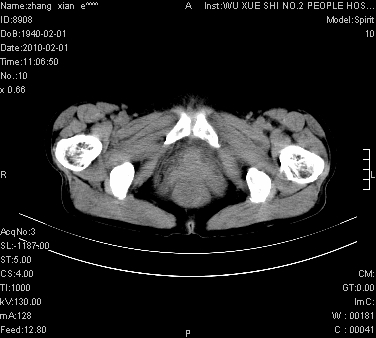

标题: CT24434:70岁 女 腹胀,腹水原因待查 [打印本页]

标题: CT24434:70岁 女 腹胀,腹水原因待查

大量腹水,脾脏囊性占位,子宫颈占位,右侧腹股沟淋巴结肿大,建议+c,先查妇科。

腹盆腔大量积液,子宫增大,子宫颈增大外形不规则,内见低密度影,膀胱后壁显示不清,右腹股沟肿大淋巴结,脾脏囊性占位,子宫颈占位,子宫颈癌?建议增强。

腹盆腔大量积液,子宫增大,子宫颈增大外形不规则,内见低密度影,膀胱后壁显示不清,右腹股沟肿大淋巴结,脾脏囊性占位,子宫颈占位,子宫颈癌?建议增强。支持!